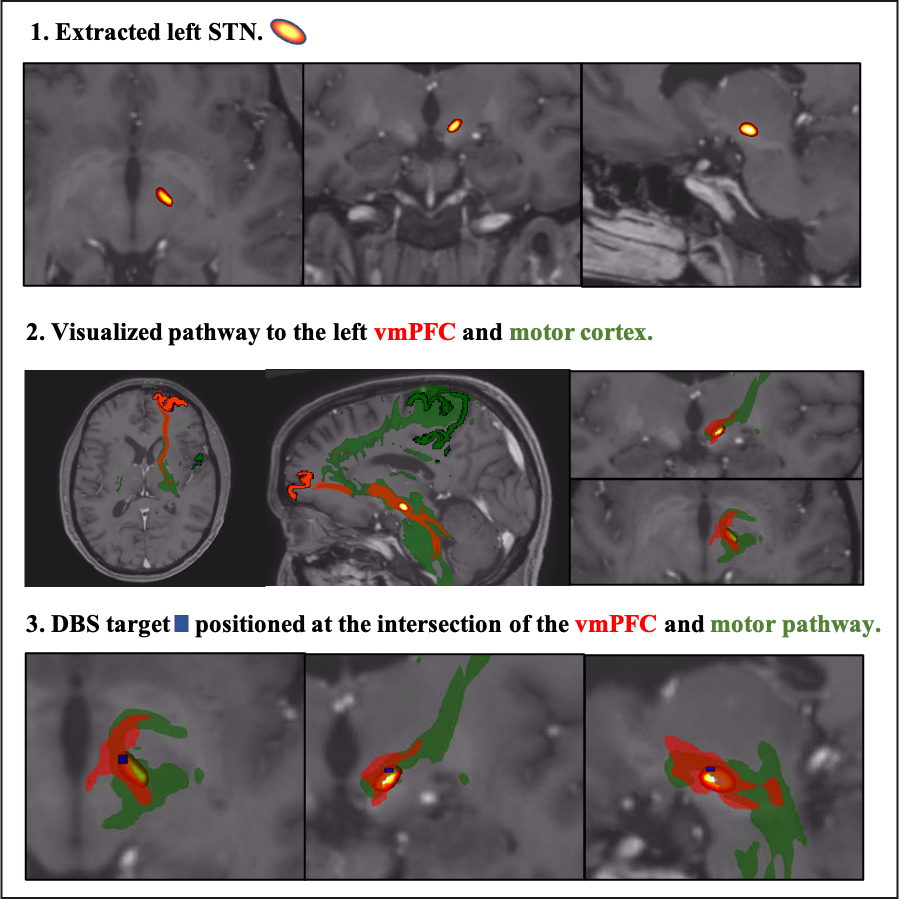

Objective: Prospective tractography-guided DBS targeting of the left STN-vmPFC and primary motor pathway to improve apathy alongside motor symptoms in PD.

Method: We used probabilistic tractography to model the left STN-vmPFC and primary motor pathways pre-surgery to define the optimal surgical STN DBS target at their intersection. DBS parameter programming followed standard clinical protocol. After 6 months of therapeutic DBS, we assessed the therapeutic response. The patient was a 51-year-old male with 14 years of PD. His pre-surgical levodopa response was a reduction of 24 points on the MDS-UPDRS III (29 OFF med to 5 ON med, -83%) and a 7-point reduction on the SAS apathy scale (21 OFF med to 14 ON med, -33%).

Results: We were able to plan a surgical target at the intersection of the motor and vmPFC pathway, Fig 1. Post-surgical assessment of the electrode placement showed that the initial target was stimulated with the current therapeutic settings (Fig 2B). The patient reported a substantial reduction in apathy symptoms, along with an 81% decrease in medication use with these settings (ON med, ON stim). At the 6-month follow-up, there was a 6-point reduction in the SAS (from 21 OFF med to 15 OFF med/ON stim, -29%) and a 20-point improvement on the MDS-UPDRS III (29 OFF med to 9 OFF med/ON stim, -69%).

Fig 1.